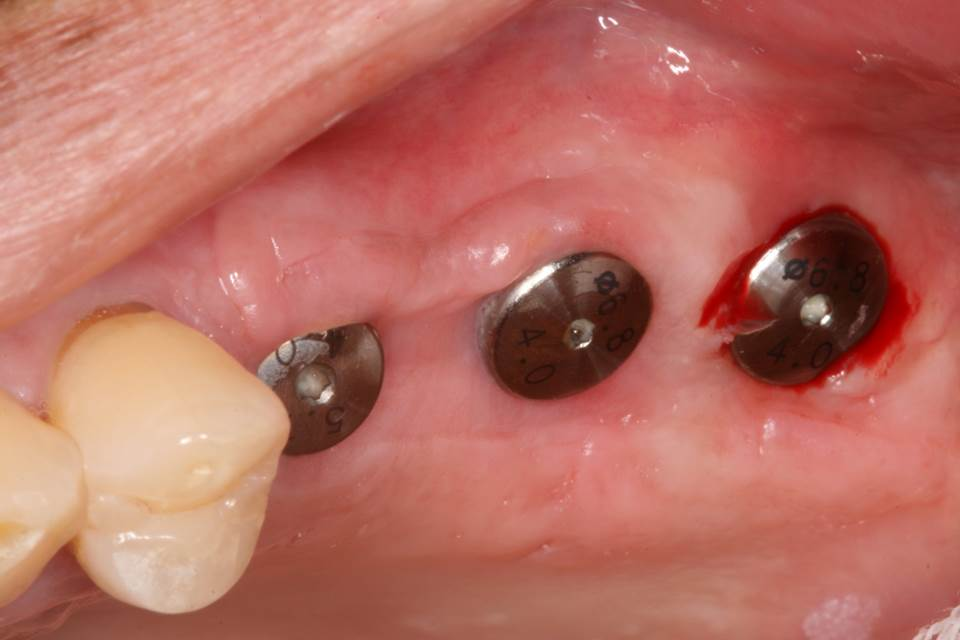

Soft tissue healing at 2nd surgery.

Removal of titanium membrane after 10 weeks.

Note the excellent bone formation underneath the titanium membrane.

The implants were uncovered by removing the excess bone formed on top of the implants.